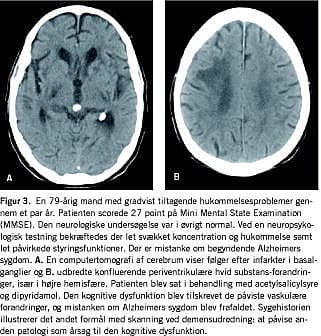

Ændring i diagnose og behandling som følge af skanning er i denne undersøgelse væsentlig højere end de 10-20%, der er fundet i tidligere studier [5, 6, 18]. Selv om to af disse studier var retrospektive, blev diagnose og behandling besluttet ved konsensus af klinikere i modsætning til i dette studie, hvor ændringer i diagnose og dermed behandling fulgte strikte fastlagte kriterier, herunder diagnostiske forskningskriterier for VaD [10], appliceret retrospektivt på journalmateriale. Dermed afspejler dette studie muligvis ikke til fulde den daglige kliniske diagnosticeringsproces. For eksempel var der i alt 99 patienter, som ikke opfyldte kriterierne for VaD, men som havde betydende CVD på skanningen. Af disse patienter havde 32 alligevel symptomer, der var forenelige med CVD (heraf 14 med akut debut eller fokale lateraliserede udfald), og en klinisk konsensus ville muligvis inkludere disse i VaD-gruppen. Dette ville medføre et fald i diagnoseændringer fra 37% til 28% og et tilsvarende fald fra 33% til 23% i behandlingsændringer. Det skal dog understreges, at de øvrige 67 patienter med CVD på skanningen ikke havde symptomer (ud over kognitiv dysfunktion), der kunne tyde på CVD, og skanning var derfor af afgørende betydning for afdækning af denne patologi (Figur 3 ).